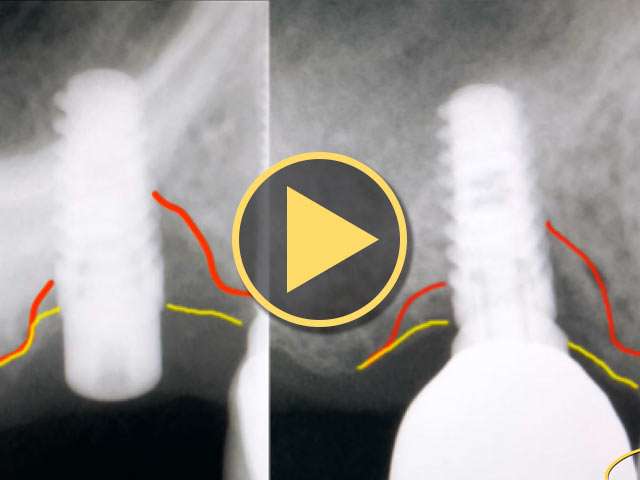

Mike Shulman, DDS, of Atlantic Dental Implant Seminars (ADIS), shares radiographs of before and after LightScalpel CO2 laser assisted peri-implantitis treatments. See bone-reestablishment in before and after radiographs.